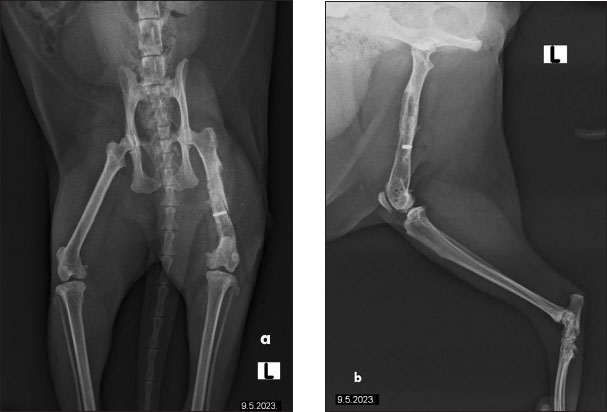

The cat had undergone orthopedic surgery 4 years ago, during which a plate was placed due to a femoral fracture (Fig. 2). Despite the surgery, the patient continued to show signs of discomfort, necessitating further diagnostics and therapy. During the examination at the radiology clinic, the cat showed signs of lameness and pain. The clinical examination revealed muscle atrophy of the left leg and pain on extension and flexion. Radiographic imaging of the pelvis and left femur revealed changes associated with the implant. Removal of the implant was recommended and subsequently performed. Figure 3 shows the radiographs of the cat’s left femur post-plate removal, showing 1 screw remaining in situ. Increased transparency in the medullary cavity indicates the need for LT to enhance healing and promote tissue regeneration.

Fig. 3. Radiographs of a cat’s left femur showing (a) a ventrodorsal and (b) a mediolateral view post-plate removal, with one screw remaining in situ. Increased medullary cavity transparency highlights the need for LT to support bone healing and tissue regeneration.